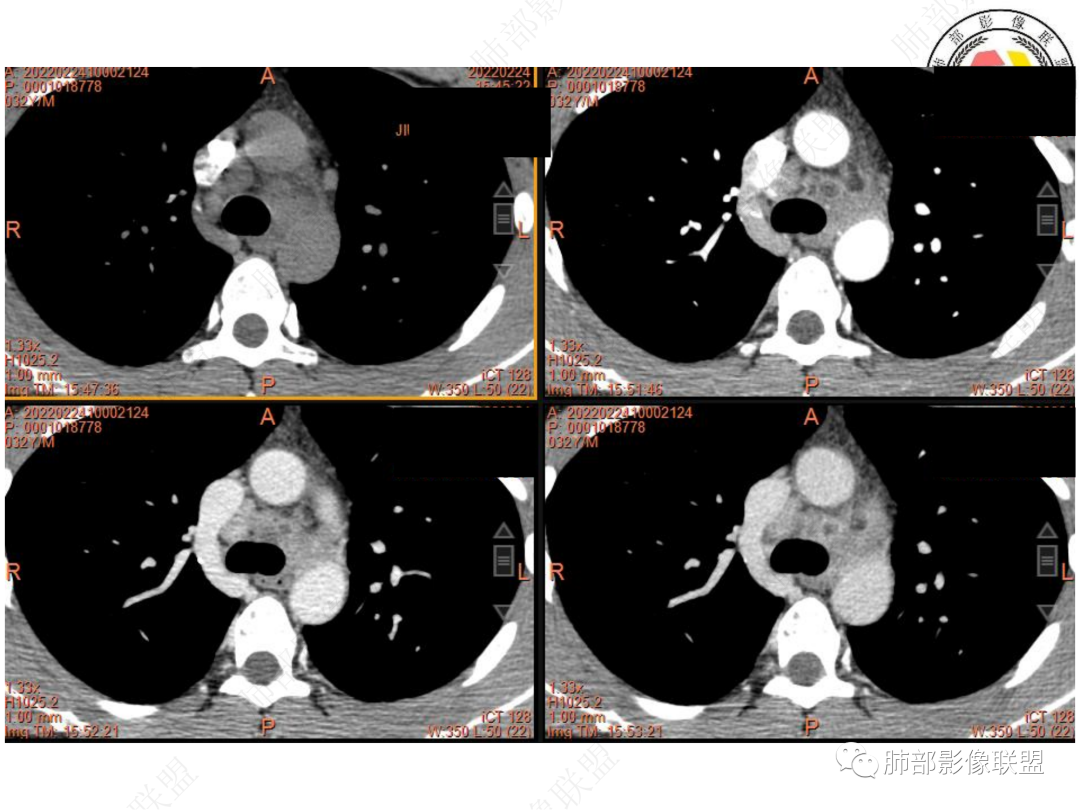

左肺门及纵隔内多发淋巴结肿大,大部分淋巴结显示融合,强化不均匀,内见低密度区,疑液化坏死。纵隔内淋巴结部分周围脂肪间隙不清晰。大血管及左肺主支气管未见受侵改变。

4. 复习文献可知:淋巴结结核的强化特征与其病理改变密切相关,当淋巴结出现干酪样坏死时呈环形强化。有研究认为成人纵隔淋巴结结核具有优势解剖分布部位,在MSCT上淋巴结的密度不均匀比率明显高于纵隔淋巴结转移瘤,增强平衡期以环形强化、分隔样强化、均匀强化为主要表现,并多种强化方式共存。纵隔淋巴结转移瘤可包绕邻近血管,邻近纵隔组织受累及时见强化。然而PET-CT尚且难以区分。

5. 此病例青年男性,纵隔淋巴结环形强化,易先入为主诊断结核。但左肺下叶背段病灶密度均匀,强化明显,整体具备膨隆感,缺少炎性病灶的平直征,病灶周围未见卫星灶,应想到新生物可能。纵隔及左肺门肿大淋巴结,虽有部分淋巴结环形强化特点,但是部分淋巴结周围血管脂肪间隙小时、密度增高,强化明显。至此,亦可与结核的环形强化区分开来。尽管患者年轻,但恶性征象出现时,仍应当高度警惕。